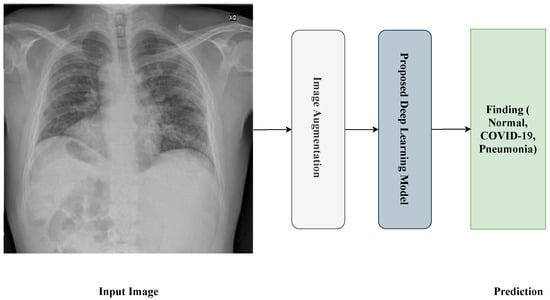

Figure 1 shows the proposed framework for the detection process. The framework passes through four steps:

• Reading and resizing process of the X-ray image.

• Image-augmentation process.

• Training process.

• Prediction process.

Transfer learning [58] is a machine learning technique based on the re-use of existing pre-trained models that are trained on large-scale datasets for new tasks. Using the transfer learning technique for your dataset means you re-use the feature extraction part from the pre-trained model, which means our model just does the classification part and we do not need to extract the feature part. In our proposed model, we use transfer learning based on various pre-trained models, one at a time, like Xception, Inception-V3, ResNet50, VGG19, DenseNet201, and InceptionResNet-v2. Then, we feed the extracted feature into many layers/models: Average-Pooling2D, Flatten, Dense, and Dropout. We use Dense with the ‘softmax’ activation function as the output layer. Figure 5 shows the transfer learning of the proposed model.

Figure 1. General framework of the proposed approach.